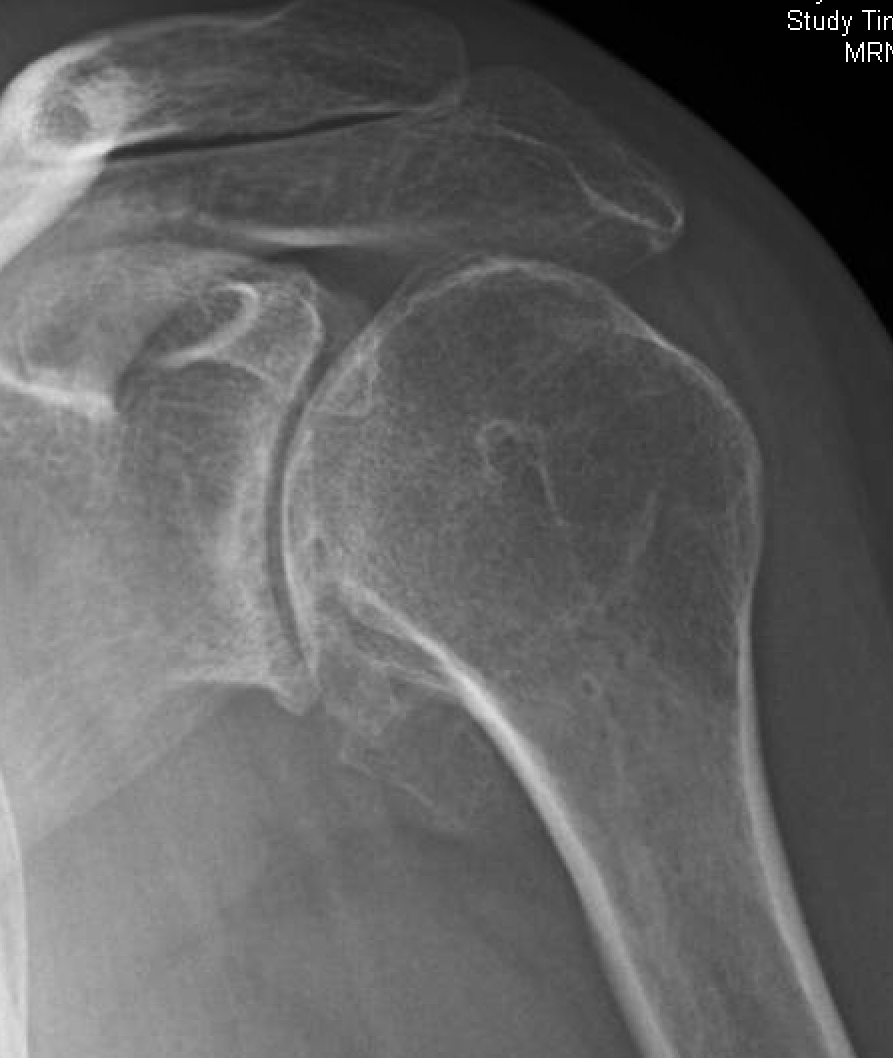

Reverse Shoulder Replacement Diagnostic Investigations Shoulder Surgery Gone Wrong Dislocation, infection, implant loosening from bone, and dissociation. The most common modes of failure for reverse shoulder replacements are: Reverse total shoulder arthroplasty (rtsa) is a terrific new tool, but failures invariably occur due to infection, instability, baseplate. One of the more common rotator cuff problems is a tear of the tendon of the rotator cuff. Rotator cuff problems are. Shoulder Surgery Gone Wrong.